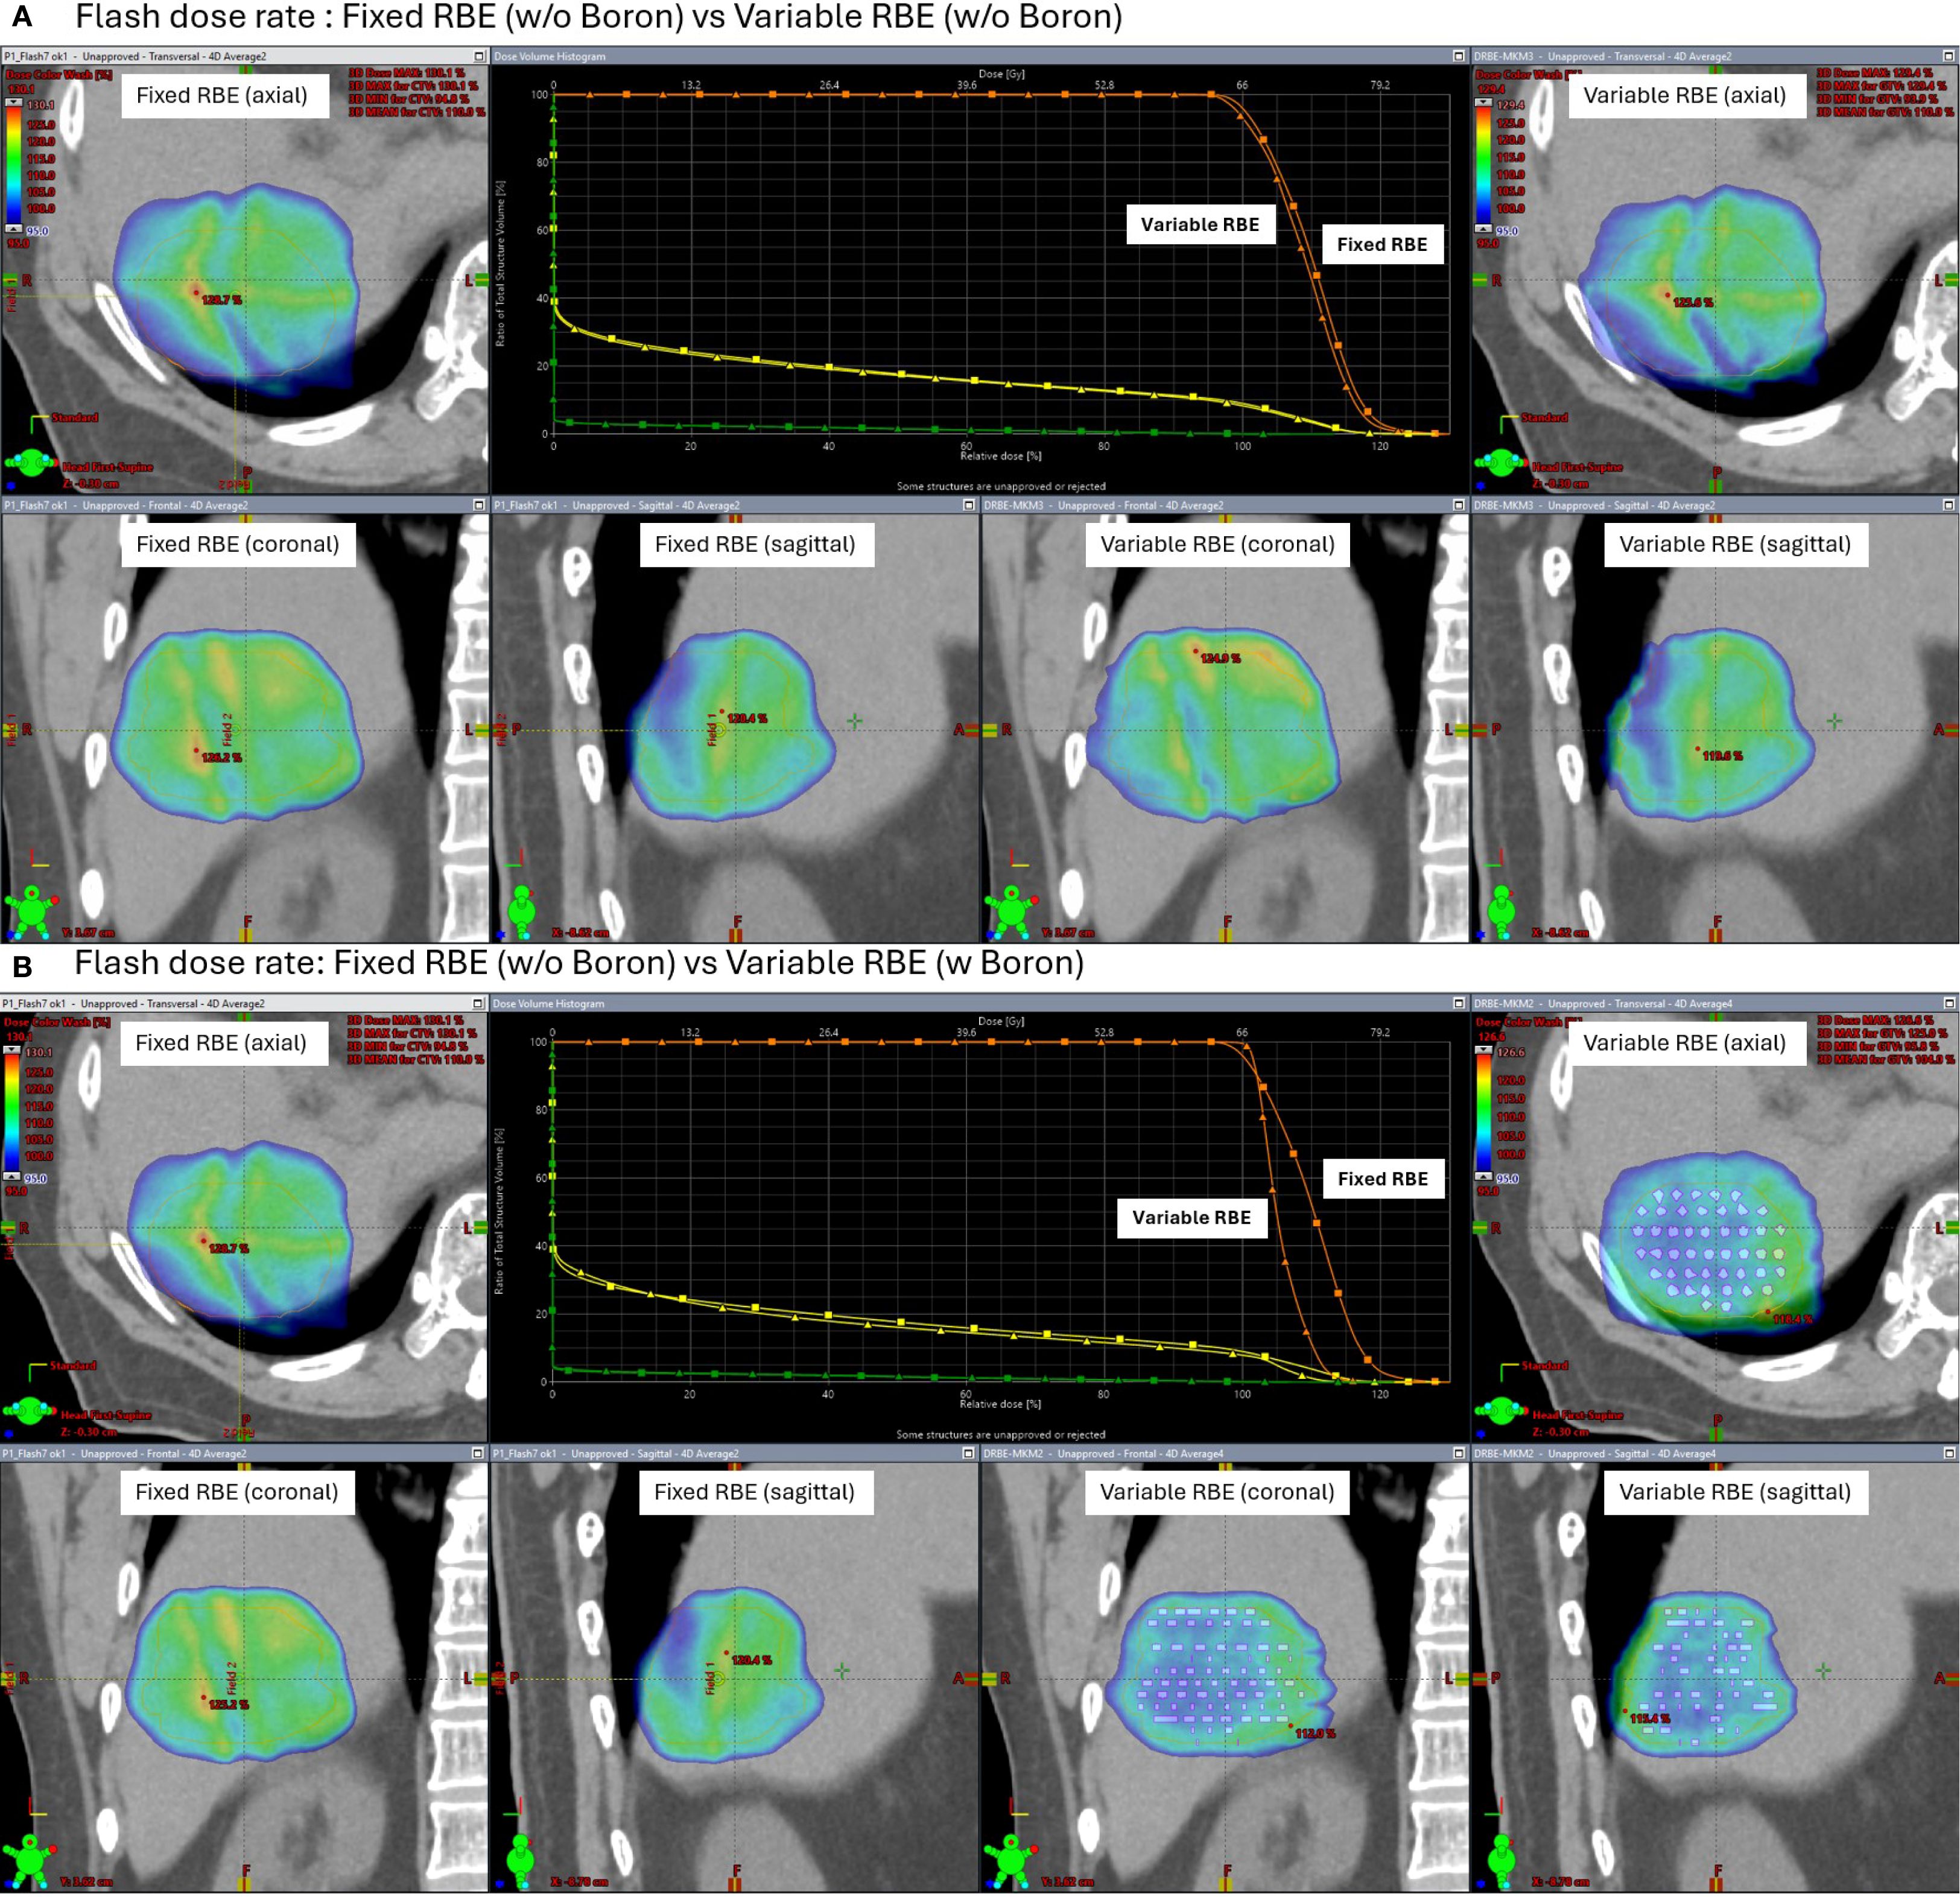

Under FLASH dose-rate conditions (Figure 8), the difference between fixed and variable RBE distributions was reduced even without the insert suggesting that FLASH delivery may inherently mitigate LET-driven dose variations. When the high-density region was added under FLASH, further improvement in dose homogeneity was observed, reinforcing the idea that both dose rate and local stopping power changes can influence biological dose shaping.

Figure 8

Panel A and B depict comparisons between fixed and variable relative biological effectiveness (RBE) at flash dose rates with and without Boron. Each panel includes CT images in axial, coronal, and sagittal views, highlighting dose distributions with color maps. A central graph shows dose-response curves comparing fixed and variable RBE metrics. Differences in dose distributions are visibly marked in the panels, emphasizing the impact of Boron.

Figure 8. Simulated axial dose distributions and DVH under FLASH proton therapy (200 MU/spot). Comparisons are shown between fixed RBE and variable RBE models, both without (A) and with (B) a high-density boron insert in the clinical target volume (CTV). FLASH conditions reduce fixed-variable RBE differences, and the high-density boron insert region further improves biological dose uniformity.